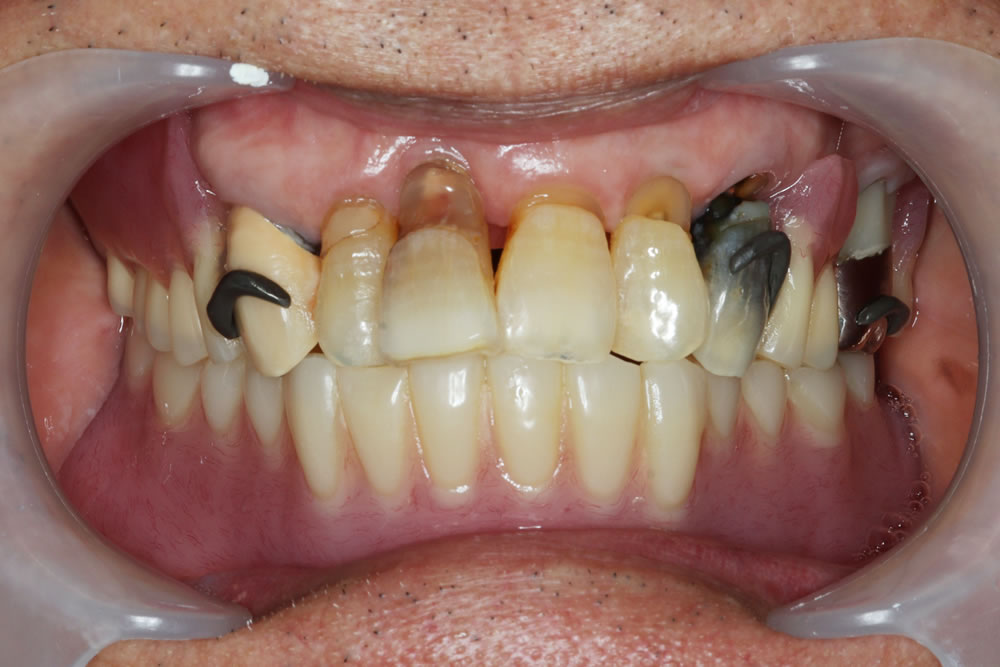

コピーデンチャーを用いて下顎総義歯を作り変えた症例

こちらの患者さまは、他院で総義歯を作製したものの「噛めない」「外れやすい」という状態が続き、入れ歯の作り直しを希望され来院されました。特に下顎の義歯が安定せず、日常生活にも支障が出ていたとのことです。

初診時のお口の状態

診察したところ、下顎の顎堤吸収(入れ歯を支える歯槽骨が痩せてしまう状態)が進行し、顎の骨の高さが全体的に低くなっていました。このような顎堤の形態では、通常の総義歯は吸着が得られにくく、義歯の安定が非常に難しい症例となります。

前歯以外の歯は目立たないこともあり、そのままで放置されている方も多いように感じます。しかし、歯を長期間抜けた状態にしておくと、少しずつ歯が移動して歯並びや咬み合わせが悪くなり、咬み合わせが元に戻らない「咬合崩壊」の状態になってしまいます。咬合崩壊の状態になると、治療が困難となったり、行えた場合であっても時間と費用がかかってしまうため、できるだけ早めの治療をおすすめします。症状によっては、入れ歯以外の治療法などもご提案可能ですので、ぜひ一度ご相談ください。